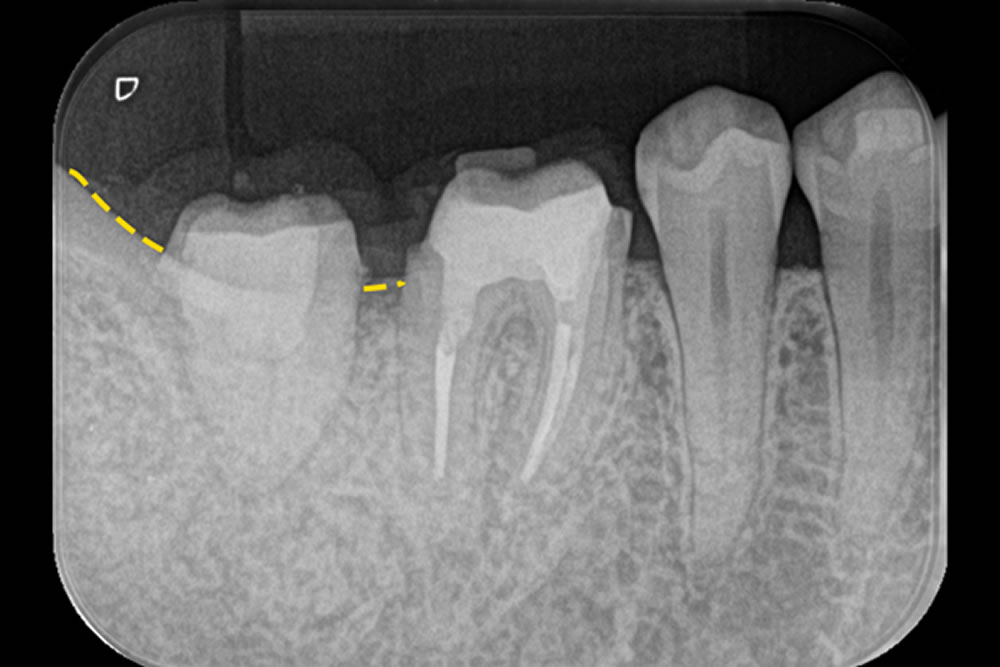

こちらの患者さまは、右下の奥歯(第2大臼歯)に歯の根の内部(神経)と歯の周囲の組織(歯周組織)の両方に問題がある複雑な状態でした。治療は、まず根の中の感染をしっかり取り除く「根管治療」を最初に行い、その効果を確認した後、歯周組織を回復させる再生治療を実施しました。

手術では、歯ぐきをできるだけ温存しながら丁寧に開く「SPPF(Simplified Papilla Preservation Flap)」という方法を採用しました。この術式は、歯と歯の間にある歯ぐき(乳頭部)を可能な限り残すことで、治療後の見た目や回復を良好に保つことができるのが特徴です。

特に、隣り合う第1大臼歯との間では、血液の流れを妨げずに治癒を促すため、切開の方向や位置を工夫して手術を行いました。術後2年半が経過しましたが、治療部位は安定しており、良好な状態を保っています。